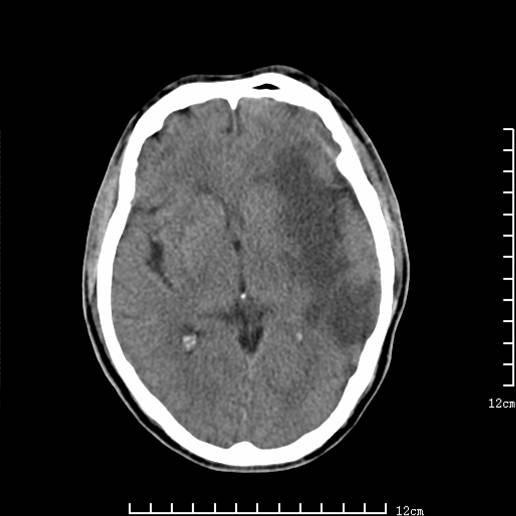

以下图像分别是3月25日凌晨及下午图像、3月27日、4月16日的ct图像。

4月16日

4月16日ct复查:符合出血性脑梗塞表现。

资料齐全,符合脑梗塞溶栓治疗后,血管再通而致的出血性脑梗塞。

支持出血性脑梗塞,可能因血管再通后,再灌注损伤所致。

4月16日ct复查:符合出血性脑梗塞表现